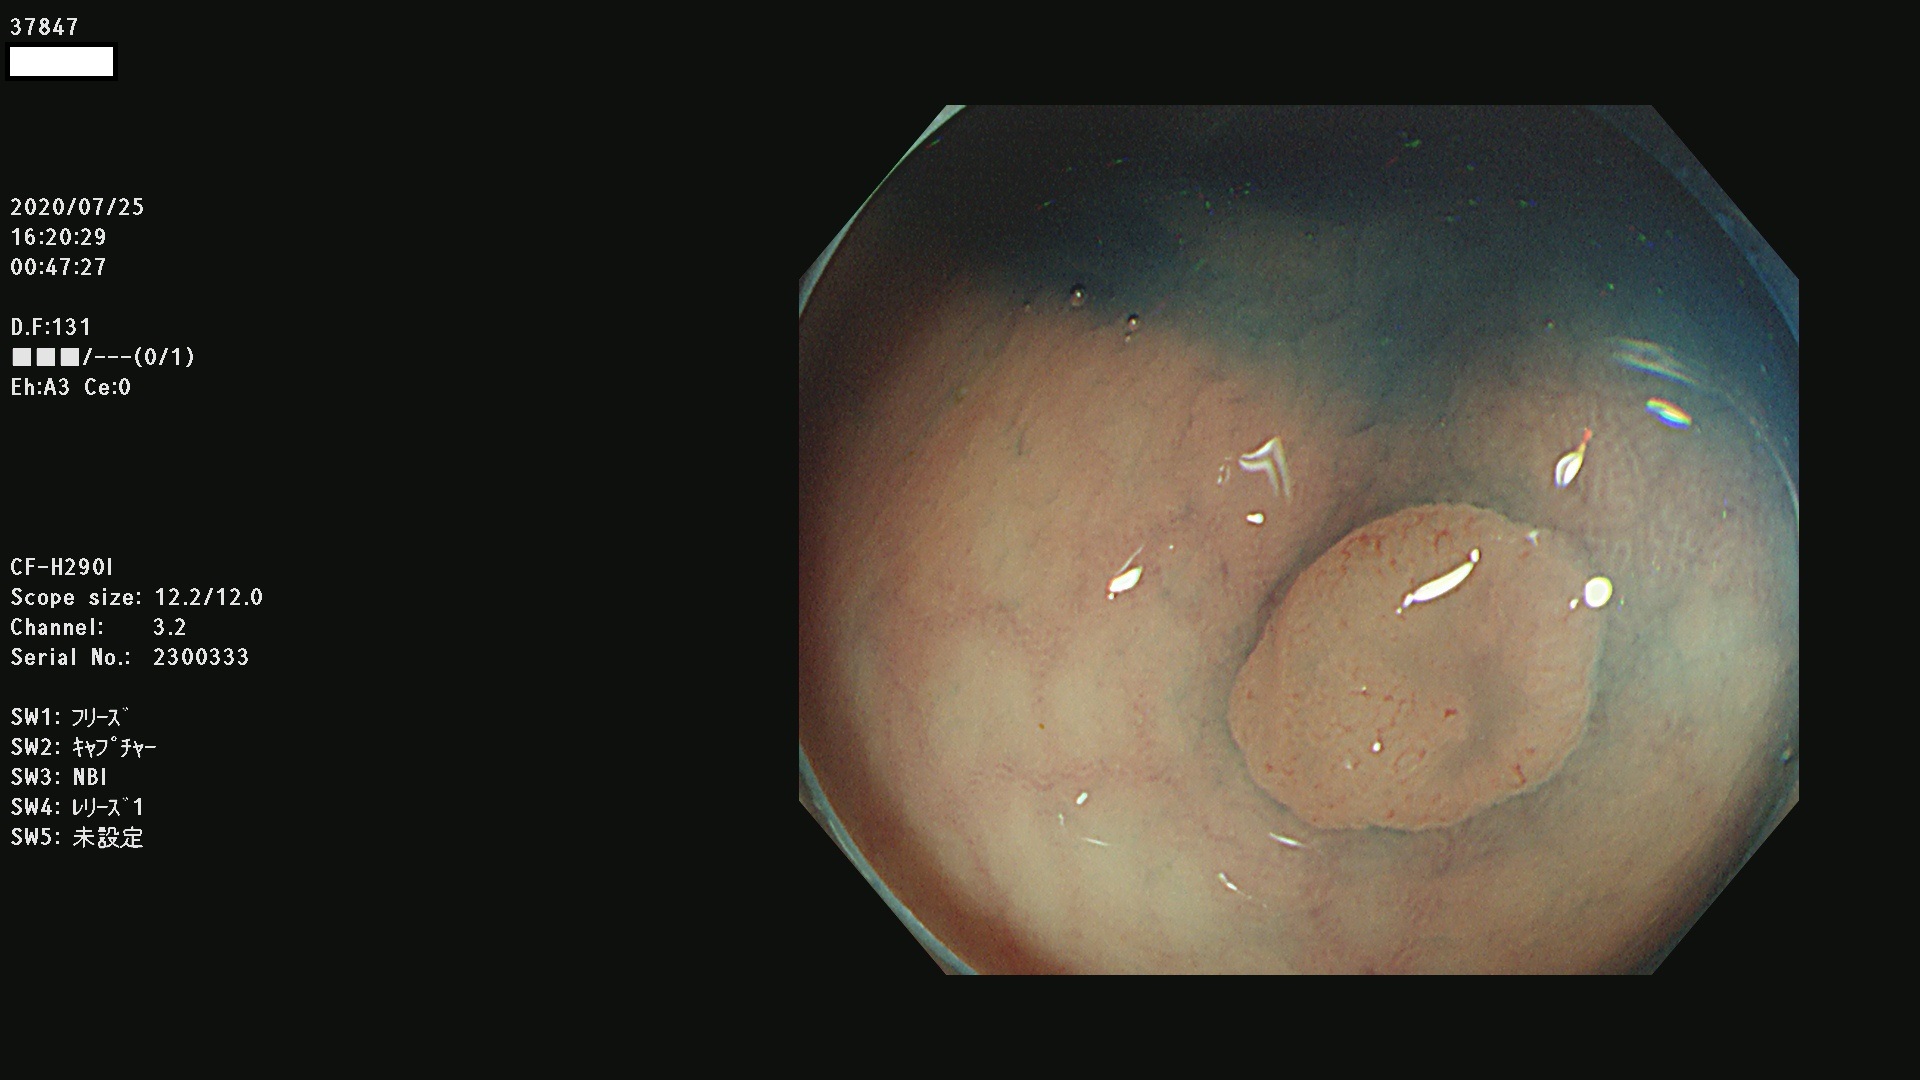

腺腫発見率 75 % (カルテ番号 37800〜37899の100名の方の検査結果で集計)大腸癌検診最新情報

以下のカルテ番号の方に腺腫(Adenoma,Group3〜5)が見つかりました(集計法)

37800(SSAPのみ) 37801 37802 37803 37804 37805 37806 37807 37808 37809(SSAPのみ) 37810 37811 37812 37813 37814 37815 37817 37818 37819 37820 37821 37822 37824 37825 37826 37827 37828 37829 37832 37833 37836 37837(SSAPのみ) 37839 37840 37842 37844 37845(SSAPのみ) 37847 37849 37850 37851 37852 37853(SSAPのみ) 37855 37856 37857 37860 37861 37862 37863 37864 37867 37868 37871 37874 37876 37877 37879 37880 37881 37882 37883 37886 37887 37888 37889 37890 37891 37892 37893 37894 37896 37897 37898 37899

発見困難で危険性の高い平坦型病変(上記100名より抽出) ![]()